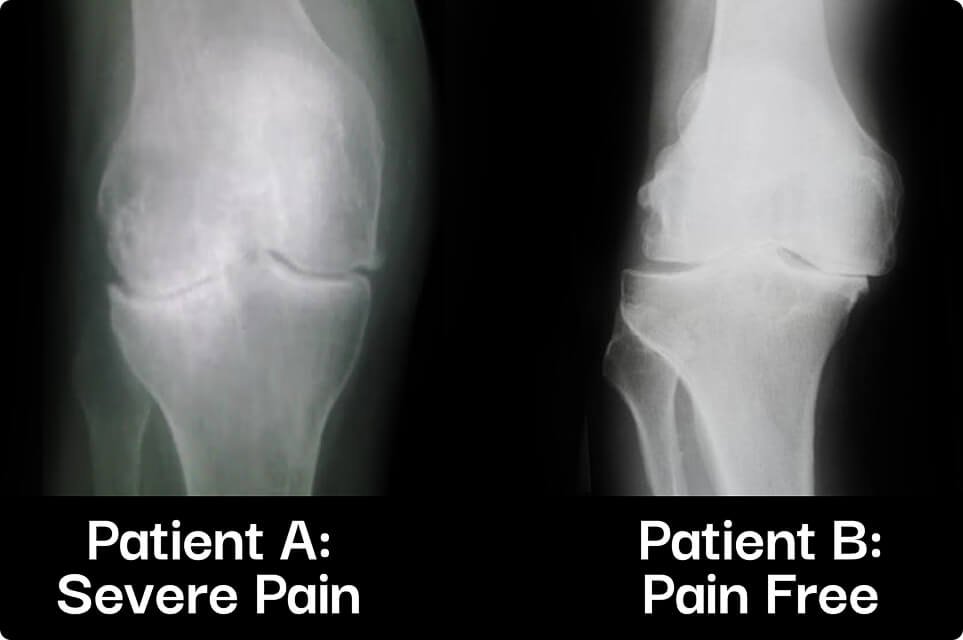

xrays from two different patients

76% of pain-free individuals show the same joint wear as those with chronic pain.

What if I told you that the stiffness, soreness, and burning discomfort in your knees, hips, and shoulders isn't primarily caused by worn-down cartilage?

It sounds shocking, but recent research from Harvard University confirms it.